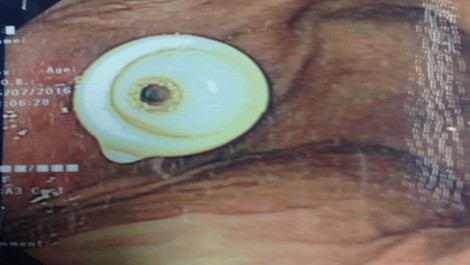

Bé Anh đã mở thông dạ dày. Ảnh: BVCC

Tháng 7/2016, các bác sĩ Bệnh viện Nhi Trung Ương đã mời Ths. Chu Nhật Minh – Trưởng khoa Nội soi – Bệnh viện Hữu nghị Việt Đức sang hội chẩn. BS. Minh cho biết: Bé đã được mở thông dạ dày vì thức ăn cứ nuốt là vào phế quản: lại ho, lại sặc, lại sốt...Nội soi thấy 1 lỗ rò lớn, đã có tổ chức xơ sẹo ở 15cm cách CRT, bơm cản quang qua catheter thấy thuốc ngấm vào phế quản. Miệng thực quản ở khoảng gần 14cm cách CRT. Tâm vị ở 26cm cách CRT.

Hội chẩn ngoại: phải đưa đại tràng lên nối, sẽ rất phức tạp và khó khăn, tiên lượng nặng nề. Hoặc là đặt 1 stent - SEMS (self expandable metalic stent) cho cháu, hy vọng thức ăn sẽ ko qua lỗ rò, tổn thương sẽ dần liền lại, rồi sẽ rút bỏ stent sau.

Được biết, khi mới được 2 tuổi, mẹ em Anh đẻ đã qua đời do tai nạn giao thông. Nhà nghèo, kinh tế gia đình cũng đã kiệt quệ. Ngay khi tiếp nhận trường hợp em bé, các bác sĩ khoa Nội soi và khoa Nhi Bệnh viện Hữu nghị Việt Đức đã kêu gọi sự giúp đỡ từ xã hội và nhận được lời đáp từ hãng vật tư y tế HAT- MED. Hãng đã tài trợ cho bé 01 cái Stent miễn phí trị giá 21 triệu (SEMS được chọn của hãng S&G Biotech INC, tên là EGIS, dài 9cm, thân 4cm, đk thân 16mm, phễu dài 2,5cm, bọc silicone).

Ngày 22/8/2016, Ths. Chu Nhật Minh đã tiến hành phẫu thuật đặt Stent. Hiện tại, bé đang được điều trị tại khoa Nhi, sức khỏe đã khởi sắc và trong quá trình hồi phục.